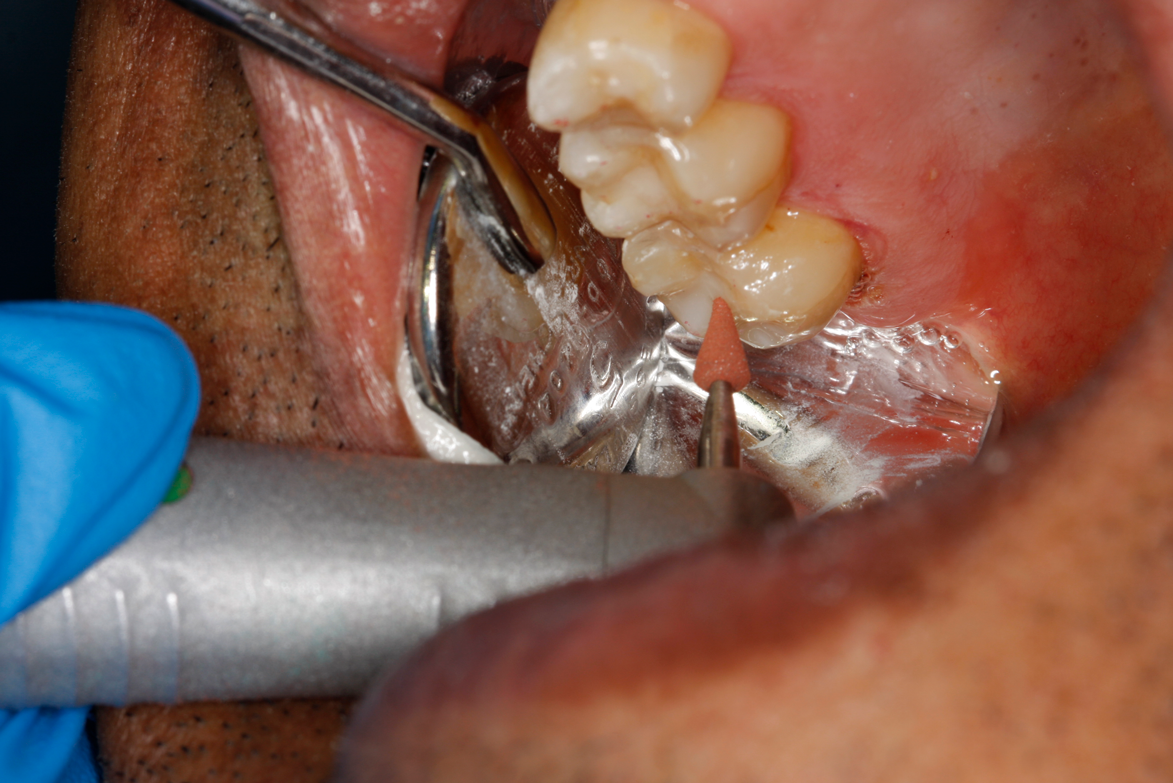

Fig 40. Brownie is shaped like a X-mas tree to prevent concaving the surface.

Figure 40

Fig 41. Brownie is used at 50,000 rpm with copious water spray on the occlusal surface, following planes defined by the acorn and X-mas tree diamonds.

Figure 41

After this dual-cure flowable's obligatory 90-second self-cure, hard sculpting with burs can begin. The Occlusinator PRO bur set (StraussUSA) was used to rapidly sculpt in planes after anatomical pits are placed at the depth of the limit stops on the burs; the clinician will appreciate the safe edges of the acorns and the safe zones on the X-mas tree burs. Figure 37 shows the medium acorn with a 50-micron diamond placing a pit where the distal marginal pit should be. It is apparent in Figure 38 that the limit stop on the acorn prevents cutting starting pits too deeply.

The safe-zoned X-mas tree with 15-micron diamond now completed the angles of the triangular and marginal ridge (Figure 39). Brownies and Greenies have convex sides requiring reshaping to a flat side so as not to create a concave surface when they are being used to final sculpt and finish (Figure 40). The straight-sided Brownie is used at 50,000 to 100,000 rpm with a copious water spray to final-shape what the diamond-coated acorn and X-mas tree bur have created (Figure 41). Brownies cut and polish composite but will only polish enamel, and are thus a true asset at a reasonable cost. Figure 42 shows the X-mas tree-shaped Greenie used at 100,000 rpm and with a copious water spray. TopDotz polisher on the latch bristle brush run at 20,000 rpm and without water will create a very high luster (Figure 43). Last, the cotton buff run dry at 20,000 rpm will afford a very high gloss (Fig- ure 44). The finished restoration is anatomic and high gloss (Figure 45 and Figure 46), and is ready for endodontic access with distal caries removed for an impervious seal. The post-treatment radiograph shows the root lesion restored and ready for endodontic treatment in this patient (Figure 47). Subsequent to endodontic therapy, margin elevation was planned to be accomplished using the dual-cure bulk-fill flowable and its requisite seal for the basement layer. Either a quartz fiber post or a Nayyar technique, again using the dual-cure flowable as the core, will provide truly minimal invasion.